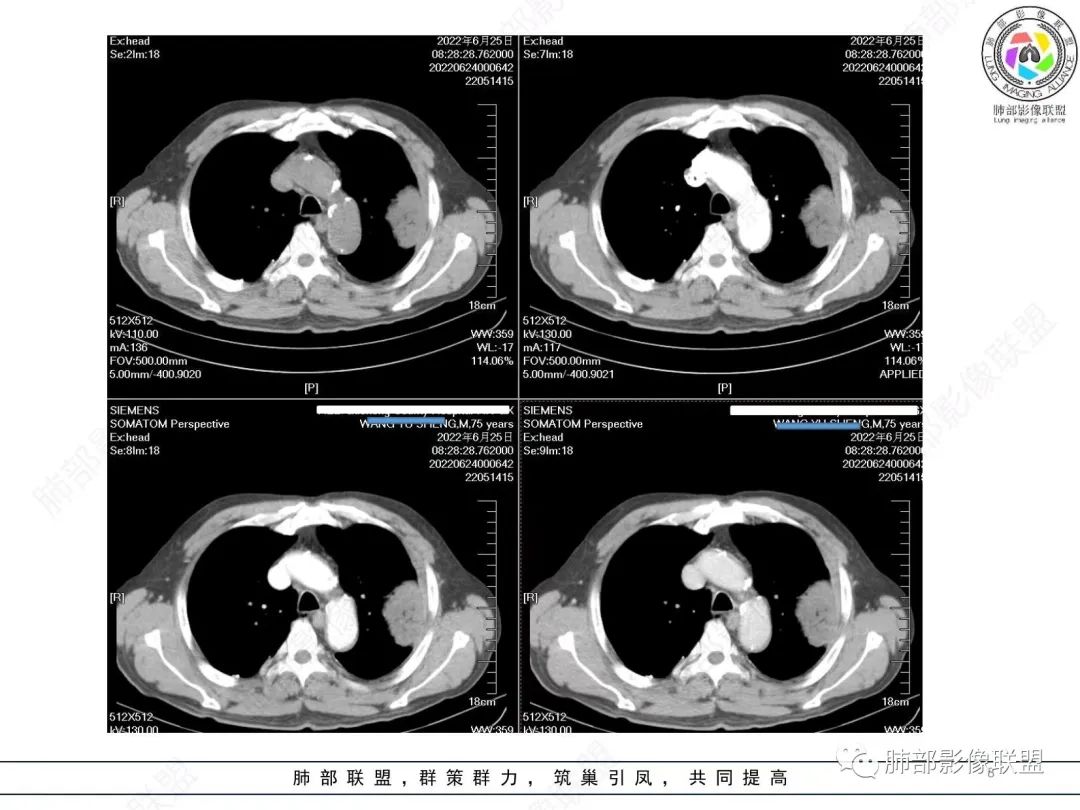

大肿块,边缘光滑,深分叶

近端支气管堵塞、推移为主

部分类似于脐凹征

内部支气管扩张

肺动脉推移为主,边缘部分进入

尘缘:

淋巴瘤肯定不符合了。

仅仅只有血管漂浮和支扩支持淋巴瘤。其他细节都是否定淋巴瘤的。

南边:

大肿块、表面光滑但深分叶,肺门侧支气管堵塞

我一开始诊断恶性,定在淋巴瘤,还觉得信心满满

回头看,内部支气管近端其实不连续,伴随肺动脉不存在

这两点就不符合

还有如果从支气管的特点考虑黏膜相关性淋巴瘤,其整体应该是边缘不清楚为主,肺炎样为主。